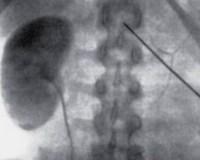

• Рентгеновские методы. С помощью экскреторной урографии определяют количество почек, их локализацию и строение. Нередко при агенезии соответствующий мочеточник и треугольник Лието также отсутствуют, иногда устье и нижняя треть мочеточника остаются интактными. Более точную картину дают ангиография почек, КТ/МРТ забрюшинного пространства, нефросцинтиграфия.